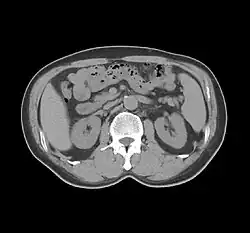

One frame of a modern CT scan of the abdomen.

In 1949, Hounsfield began work at EMI, Ltd. in Hayes, Middlesex, where he researched guided weapon systems and radar. Hounsfield incorrectly gave this date as 1951 when he wrote his autobiography which is available on the Nobel Prize website. The correct date is 10 October 1949 as stated in a biography of Hounsfield.[15] At EMI, he became interested in computers and in 1958, he helped design the first commercially available all-transistor computer made in Great Britain: the EMIDEC 1100. Shortly afterwards, he began work on the CT scanner at EMI. He continued to improve CT scanning, introducing a whole-body scanner in 1975, and was senior researcher (and after his retirement in 1984, consultant) to the laboratories.